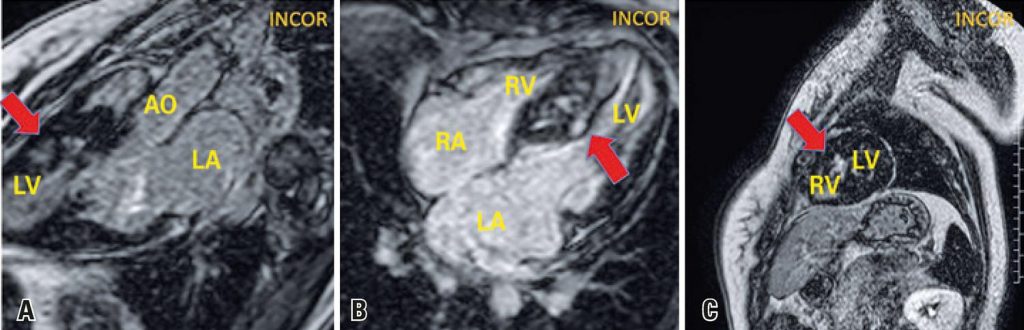

An 18-year-old female patient with hypertrophic cardiomyopathy previously asymptomatic, diagnosed in family screening, who presented progressive dyspnea even upon mild exertion two months before. She was submitted to cardiac magnetic resonance ( and ), which showed asymmetrical myocardial hypertrophy with mid-ventricular septal predominance. The most common form of obstruction of the left ventricle outflow tract in hypertrophic cardiomyopathy is subaortic obstruction,() which generally results from left ventricle outflow tract narrowing by septal hypertrophy and systolic anterior motion of the mitral valve anterior cuspid.()